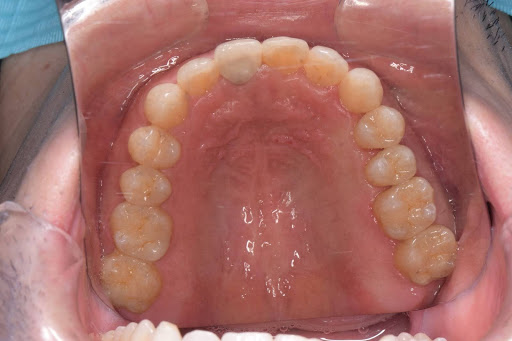

以下は症例写真です。

長年使用していた金属の詰め物を、生体親和性の高いセラミック素材に置き換えました。

天然歯のような透明感が生まれ、金属アレルギーの不安も解消されています。

<After>